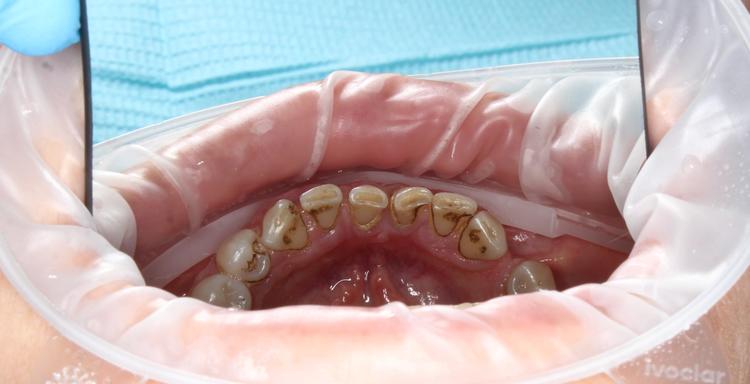

Профессиональная гигиена верхней фронтальной группы зубов

Во время процедуры удален пигментированный зубной налет и камень, проведена полировка зубов. После снятия зубных отложений можно оценить состояние зубов: видна старая пломба и кариозная полость.